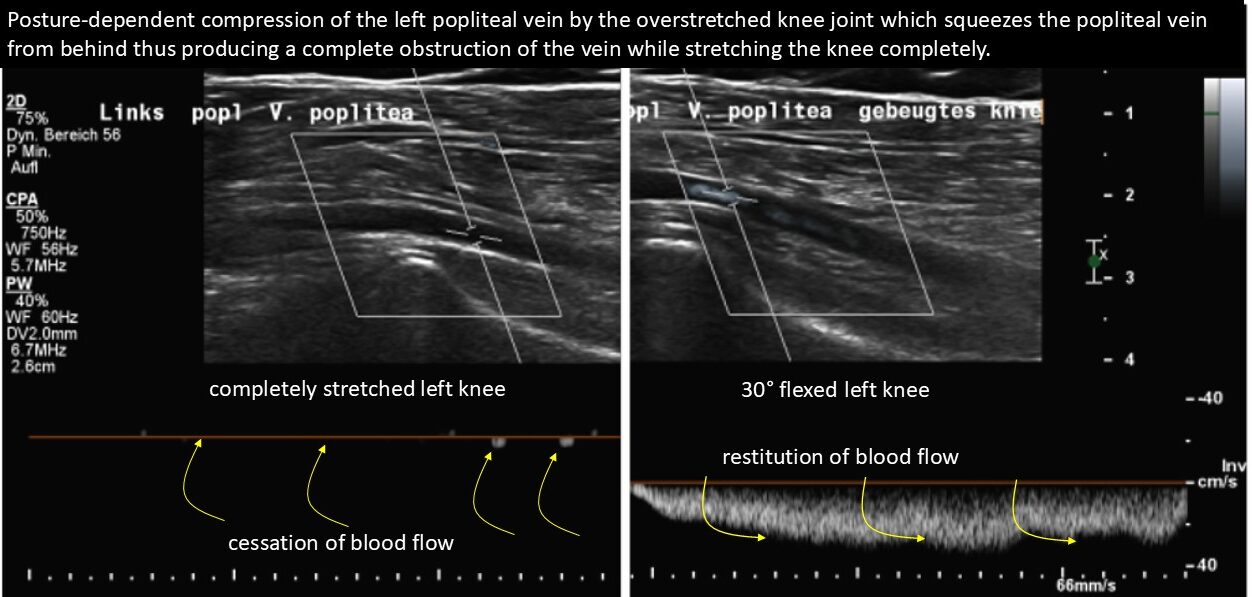

Here the complete compression of her popliteal vein is demonstrated when she fully straightened her knee. Only after flexing her knees to an angle of 30° was her peripetal venous perfusion reinstated.